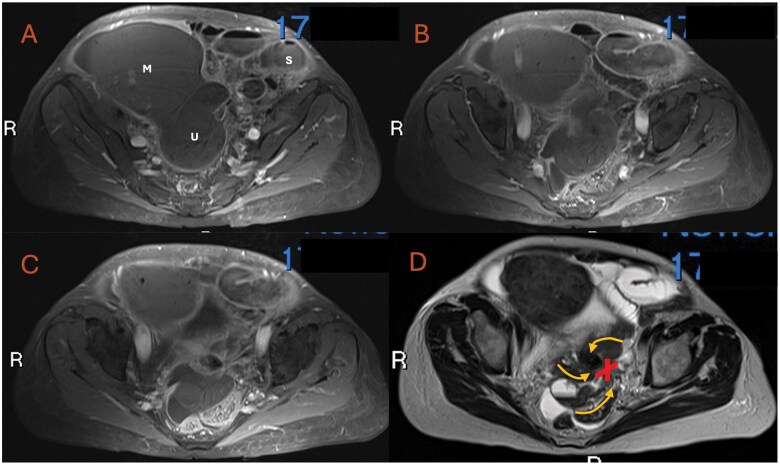

This case report describes the rare occurrence of a pre-operative radiological diagnosis of uterine torsion in the non-gravid uterus. A 78-year-old female presented with a 5-day history of worsening non-specific gastrointestinal symptoms. Her admission CT study initially reported a large adnexal mass lesion causing obstruction of neighbouring small bowel loops. Management was initiated under the presumption of a complex uterine fibroid causing local small bowel obstruction. Only a secondary radiological review-conducted due to persistent abdominal pain-identified the characteristic "whirlpool" sign of the uterine cavity and prompted the differential of uterine torsion. Contrast-enhanced MRI study further confirmed this suggestion with a lack of uterine contrast uptake and the "X-sign." The patient subsequently had an emergency laparotomy for a total abdominal hysterectomy and bilateral salpingo-oophorectomy. Intra-operative findings and further histological analysis demonstrated a distorted uterine cavity with haemorrhagic infarction, confirming a diagnosis of uterine torsion.